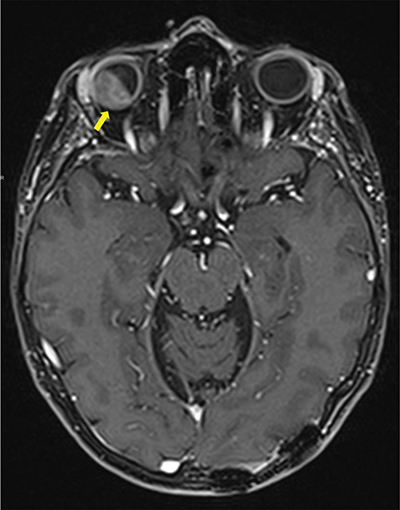

Figure 1

Contrast enhanced Axial T1 Dixon MRI-scan showing intra-orbital metastasis (arrow) invading all layers of the eyeball and the intra-conal fat.

A magnetic resonance image (MRI) demonstrated a 16.5 × 10.7 mm right intraorbital mass of superolateral topography invading all of the ocular globe layers (Figure 1), and a second medial 8 × 3.7 mm right intraorbital mass (arrow, Figure 2 T1, Figure 3 T2). The posterior sclera and the periorbital fat were invaded, with partial right retinal detachment (arrowhead, Figure 2 T1, Figure 3 T2).